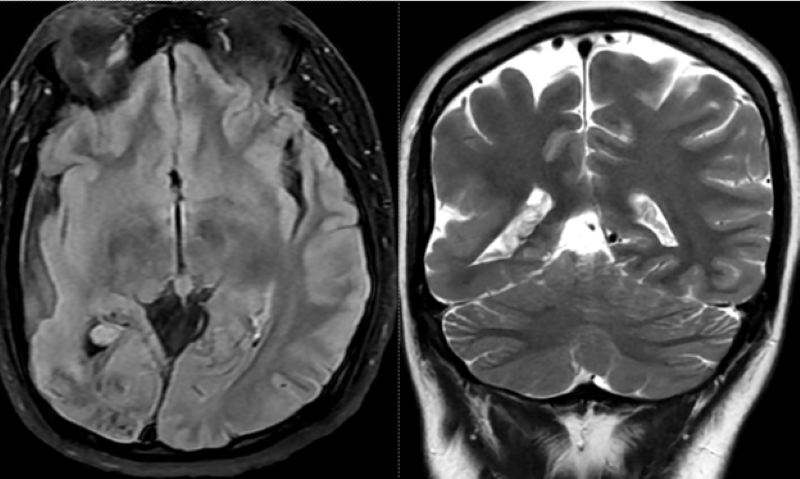

Đáng chú ý, trên phim chụp MRI sọ não phát hiện hình ảnh đám tổn thương cũ có vôi hóa, teo não thùy chẩm phải (vùng xuất phát của tia thị giác). Phì đại đám rối mạch mạc trong não thất bên phải. Thiểu sản động mạch đốt sống bên phải đoạn nội sọ.

Bất thường được phát hiện trên phim chụp MRI sọ não